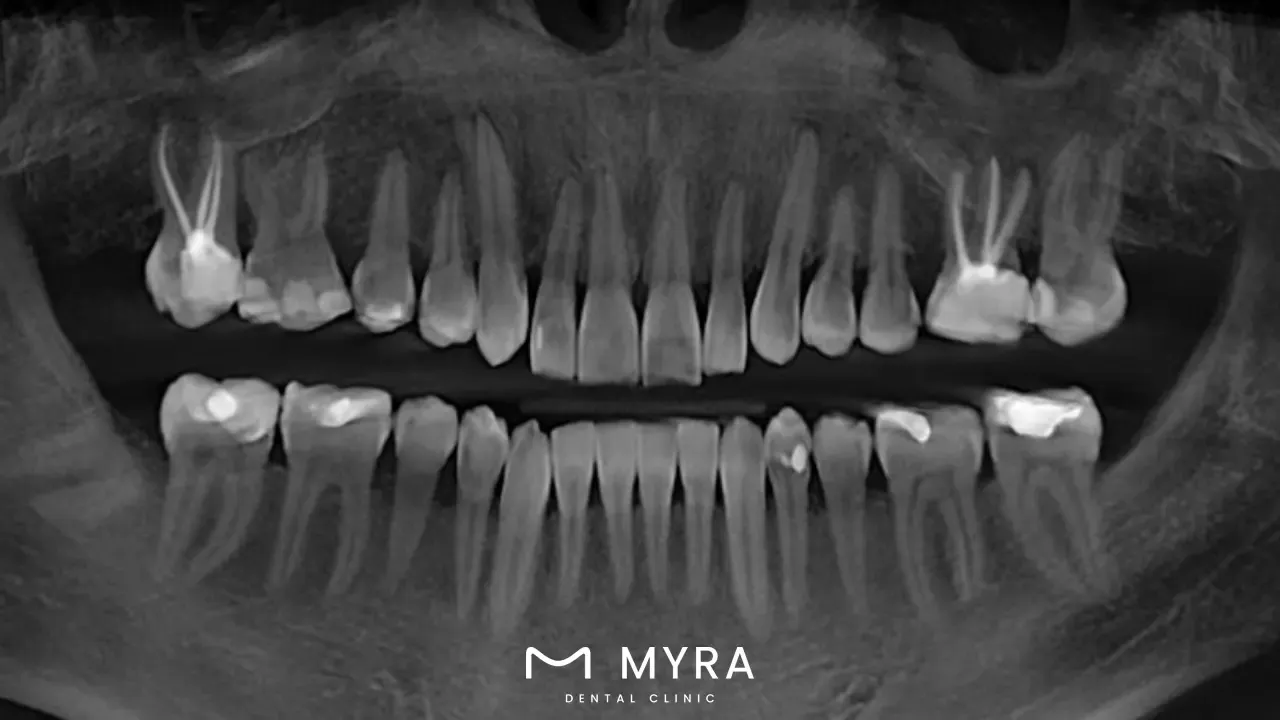

2. Dental implants

Dental implants are artificial tooth roots that are inserted into the jawbone via a surgical procedure. They are used to replace one or more lost teeth. These implants, which are mostly made of titanium, a material that is biocompatible, and are put into the jawbone in such a way as to duplicate the root structure of a tooth, are generally biocompatible.

Osseointegration is the process by which the bone grows around the implant and integrates with it; it happens over the course of time and keeps the implant firmly in place. The top of the implant is fitted with an abutment after the fusion has taken place, which makes it achievable to restore the missing tooth with a dental crown, bridge, or denture. The end result is a tooth replacement that appears and functions just like a natural tooth.

Dental implants are becoming increasingly popular as a result of their long-term durability and stability as well as their nearly natural feel and function. They not only provide a replacement that is aesthetically beautiful, but they help in protecting the bone structure, which frequently deteriorates when a tooth is lost. Bone health, oral cleanliness, and overall health all have an effect on the success and longevity of dental implants, so it's important to get a professional opinion before making the decision to get implants.

Dental implants are one of the most expensive treatments that are performed in the dentist's office; nevertheless, the fact that they last a lifetime and provide both practical and aesthetic benefits frequently make the investment worthwhile. These treatments are available in Turkey and Costa Rica, two countries that have become popular destinations for dental tourists, at prices that are significantly more affordable than in many Western countries.

Expect to pay anywhere from £400 as Osstem implant to £850 as Straumann implant for each implant in Turkey. The price of a dental implant varies depending on the brand, the material, and the experience level of the dental surgeon; but, in general, anticipate paying the required amount.

The cost of a single dental treatment implant ranges from 450,000 (£663.10) to 900,000 (£1326.20) CRC in Costa Rica. These expenses are comparable to other countries' prices.

These figures take into account both the cost of the implant itself as well as the cost of the surgical procedure required to place it. There is a chance that additional fees are going to be incurred for the crown, the abutment, and any necessary preparatory operations, such as bone grafts or sinus lifts. It's important to talk to dental clinics in these countries personally to get accurate and up-to-date pricing information, since prices change based on the economy, inflation, and other factors.